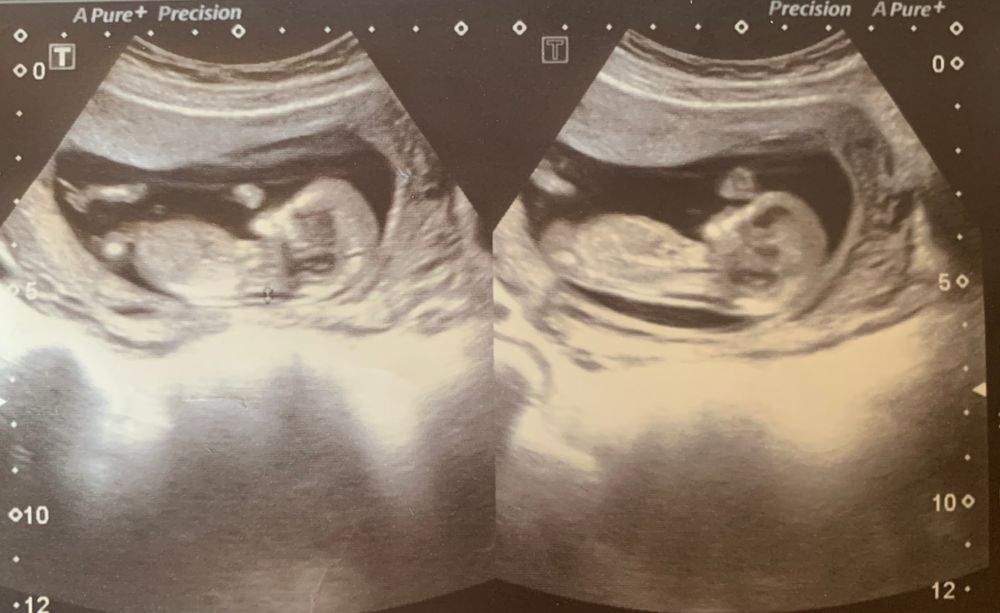

Ну девчуля же, да?😻

Если то что я вижу не 3 фото, это девочка 👧

Я могу только по половому бугорку, а его тут не видно( Ты НИПТ решила делать? Тогда ч так понимаю через 1.5 недели будет результат?

Лёся, добавила ещё одну фотку с другого ракурса. Посмотри, может, сейчас разглядишь😀 да, нипт сдала. Результат через неделю.

Сентябринхен, если это половой бугорок, то прям 99,9999% девочка. Но только если это половой бугорок 🤣 потому что на бедровую кость тоже похоже. Но у Леи тоже на сроке 11-12 недель было точно такое же узи и в итоге девочка. Я даже на бб свои предположения писала. Так что я тоже за девочку!

Но ведь на фото половой бугорок не видно....

Валерия, скажем так, сегодня на узи на миг включили область между ног и там было совсем не так все очевидно, как у сына. Плюс скорее вопрос про общую конституцию и профиль. На сравнении с сыном мне кажется очень аккуратным

не в таком положении определяют)) и не на таком сроке.

Ирина, определяют на таком сроке тоже, но достоверность спорная)

Вопрос из зала а как у нас определяется пол в профиль тела человечка если даже опытные врачи смотрят "снизу" и бывает видят фигу!!?

Алина М, снизу на таком сроке не смотрят. Там нет половых органов, а только половой бугорок, который в профиль как раз и смотрят.